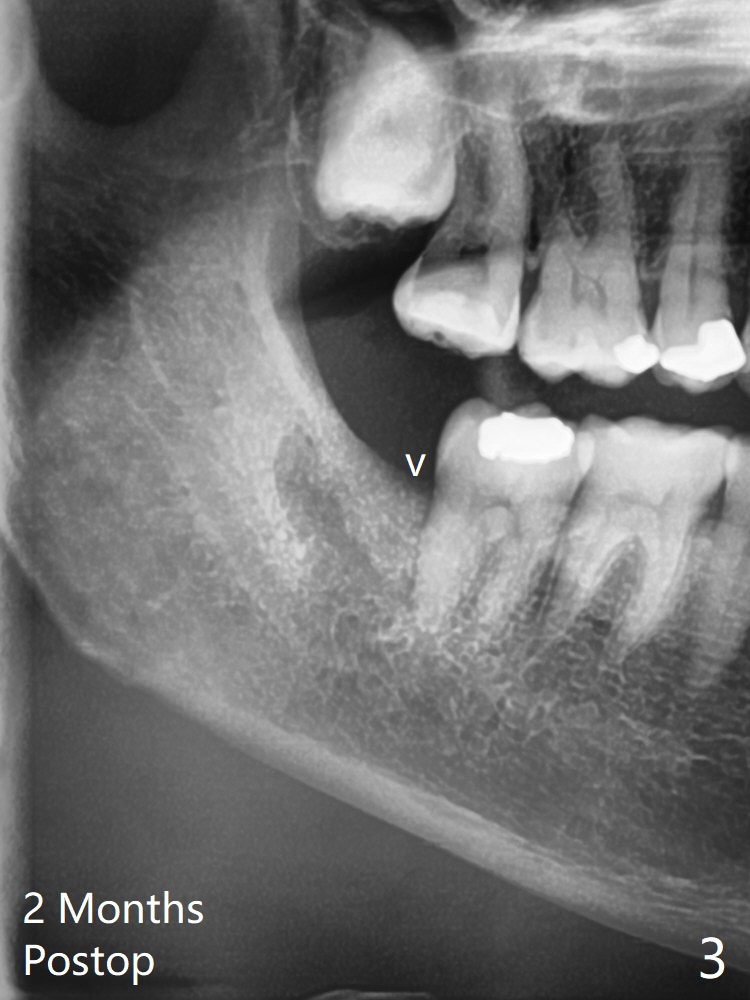

56岁女因右下智齿牙龈出血要求拔除,切开后发现智齿周围骨质吸收,有许多肉芽组织(图一:*),拔除容易,清创时远中牙龈出血,需要压迫止血,之后在牙槽窝远中,近中放置胶原塞(图二:C)和粘性骨粉(S),上面覆盖PRF,使用4-0 PGA缝线,近中伤口缝合不紧。术后两个月随访时拍摄全景片证实骨粉没有明显流失(病人抱怨术后骨粉流失,逐渐减少),第二磨牙远中没有骨板,第三磨牙近中牙槽嵴接近正常外形(图三:箭头)。Return to Plug Allograft 儿子 Xin Wei, DDS, PhD, MS 1st edition 06/07/2021, last revision 08/01/2021